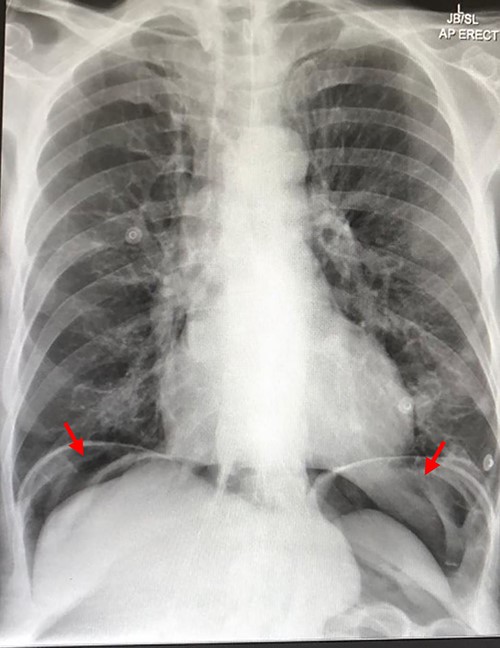

CT scan on initial presentation showing pneumoperitoneum without obvious cause. Sagittal, axial, coronal views. Arrows show pockets of free intraperitoneal air

On presentation, his temperature was 37.8°C, and he was hypotensive at 100/45 mmHg and tachypneic with a respiratory rate of 22. He was in moderate respiratory distress and was placed on 2 L oxygen via nasal prongs. On abdominal examination, mild distension was noted with lower abdominal tenderness with rebound tenderness and guarding in the right lower quadrant. He had normal leukocytes of 5 × 109 /L (N: 4.0–11 × 109/L) and lactate was normal at 1.6 mmol/L (N: 0.5–2.2 mmol/L). X-ray chest showed free air under the diaphragm suggestive of pneumoperitoneum (Fig. 1). A CT abdomen was performed showing large-volume free air suggestive of a viscous perforation and moderate volume of free fluid in the abdomen (Fig. 2). The site of perforation was not confidently established on the study. There was generalized oedema of the right side of the colon with multiple loops of dilated small bowel. His Physiological and Operative Severity Score for enumeration of Mortality and Morbidity (POSSUM) score would be 81% predicted mortality and 98.8% predicted morbidity if he were to undergo an emergent laparotomy operation. Family discussion was made, and he decided not to proceed with operative management. He was managed conservatively with piperacillin-tazobactam and decompressed with nasogastric tube insertion. As the days progressed, his abdomen became increasingly distended and tympanic, but not peritonitic. We repeated a CT chest and abdomen three days after initial admission and it was reported he had tension pneumoperitoneum (Fig. 3). CT with oral contrast was also performed to exclude an upper GI perforation.